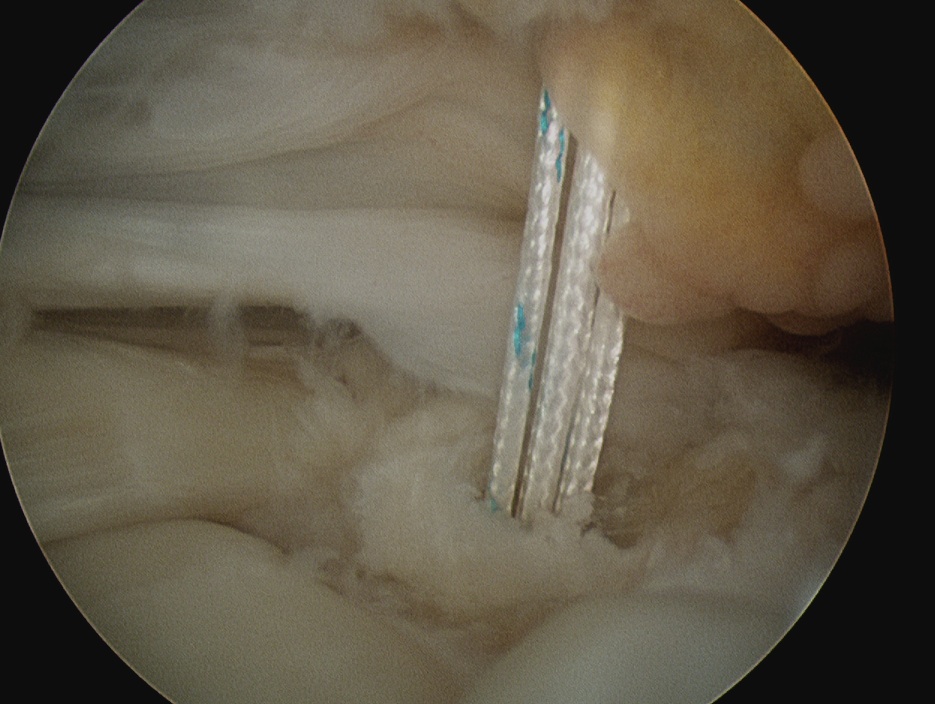

Pass sutures in lateral margin cuff

- camera posterior

- elite / scorpion / concept suture passer via lateral portal

- pass sutures through cuff anterior to posterior

- retrieve sutures through anterior portal

- retrieve via anterior portal

Double row

- either pass second lateral row of anchors or

- use foot print anchors, retrieve previous sutures

- can make suture bridge configuration